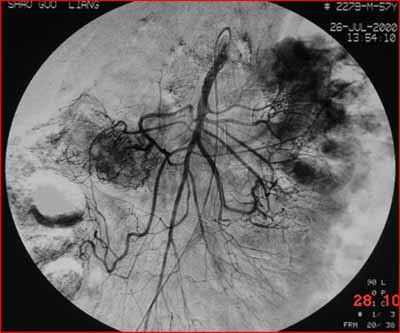

(結(jié)腸動脈造影:腫瘤染色明顯。通過造影明確供血動脈,進(jìn)行腫瘤區(qū)域的化療灌注。)

據(jù)統(tǒng)計(jì),結(jié)直腸癌術(shù)后約有40%的人會出現(xiàn)肝臟轉(zhuǎn)移,對于已有肝臟轉(zhuǎn)移的患者,傳統(tǒng)的手術(shù)更是無法徹底治療。這類病人則可用介入治療:先將幾種最有效的抗癌藥搭配在一起,然后通過導(dǎo)管技術(shù),找到腫瘤的供養(yǎng)動脈,把抗癌藥和栓塞劑直接注入腫瘤組織。這種療法主要有兩大優(yōu)勢:一方面將高濃度的藥物直接作用于局部,發(fā)揮最大的抗腫瘤作用,對全身毒副作用小,絕大部分患者能接受治療;另一方面,還可將腫瘤的供血血管阻塞,使腫瘤失去血供而“餓死”。對于術(shù)前尚未有明確肝轉(zhuǎn)移的患者,術(shù)前若用介入治療,可消滅“隱性的轉(zhuǎn)移”(單個(gè)腫瘤細(xì)胞的轉(zhuǎn)移),配合手術(shù)和術(shù)后的全身化療,復(fù)發(fā)率顯著下降。而對于術(shù)前已有肝臟轉(zhuǎn)移的患者,術(shù)前的介入治療可使轉(zhuǎn)移灶縮小,為手術(shù)提供良好的機(jī)會,再配合術(shù)后的全身化療,患者的生存率顯著提高??傊?,介入治療的出現(xiàn),為提高結(jié)直腸癌的治療效果、延長患者的生命,起到很好的作用。